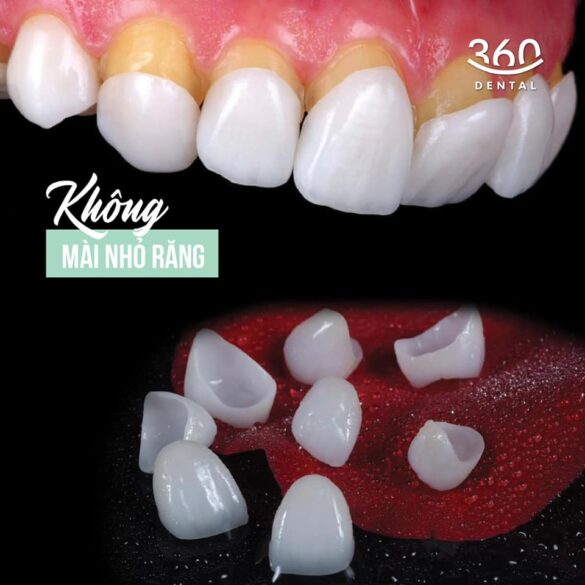

Chia sẻ một số case chuyên môn